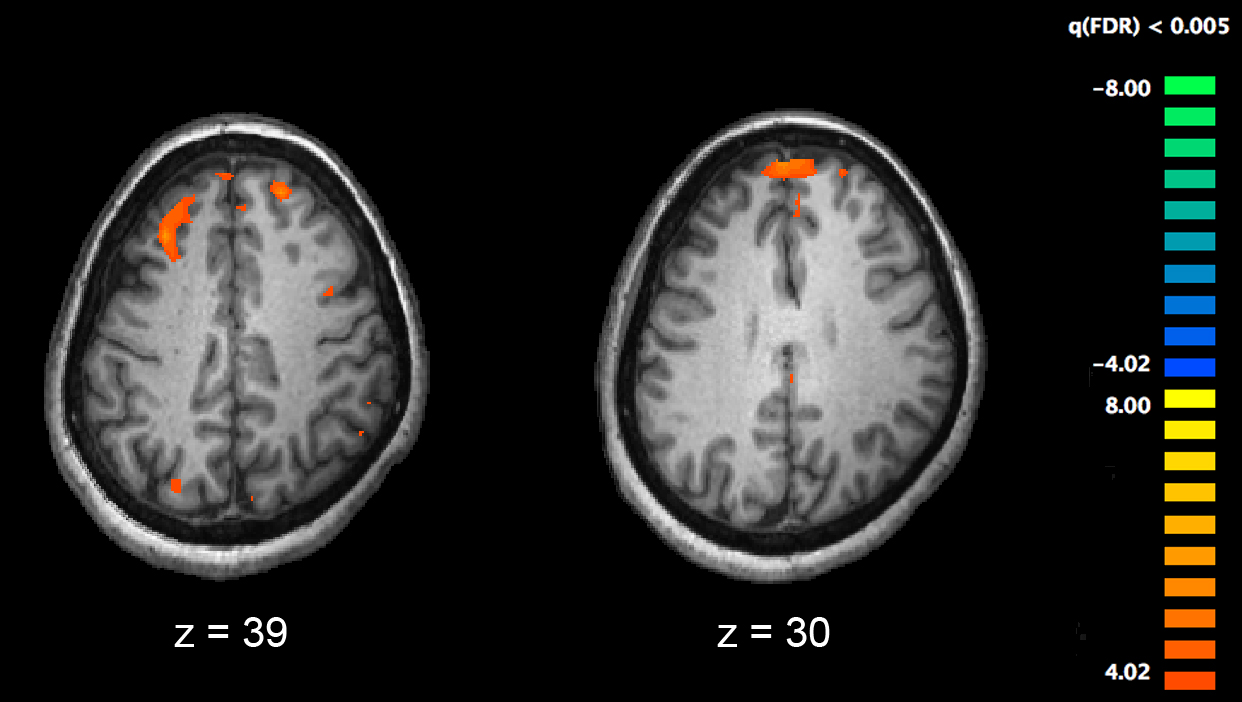

Immagine: La risonanza magnetica funzionale (fMRI) e altre tecnologie di imaging cerebrale consentono lo studio delle differenze nell’attività cerebrale in persone diagnosticate con la schizofrenia. L’immagine mostra due livelli del cervello, con aree più attive nei controlli sani che nei pazienti schizofrenici mostrati in arancione, durante uno studio fMRI sulla memoria di lavoro. Credito: Kim J, Matthews NL, Park S./PLoS One.